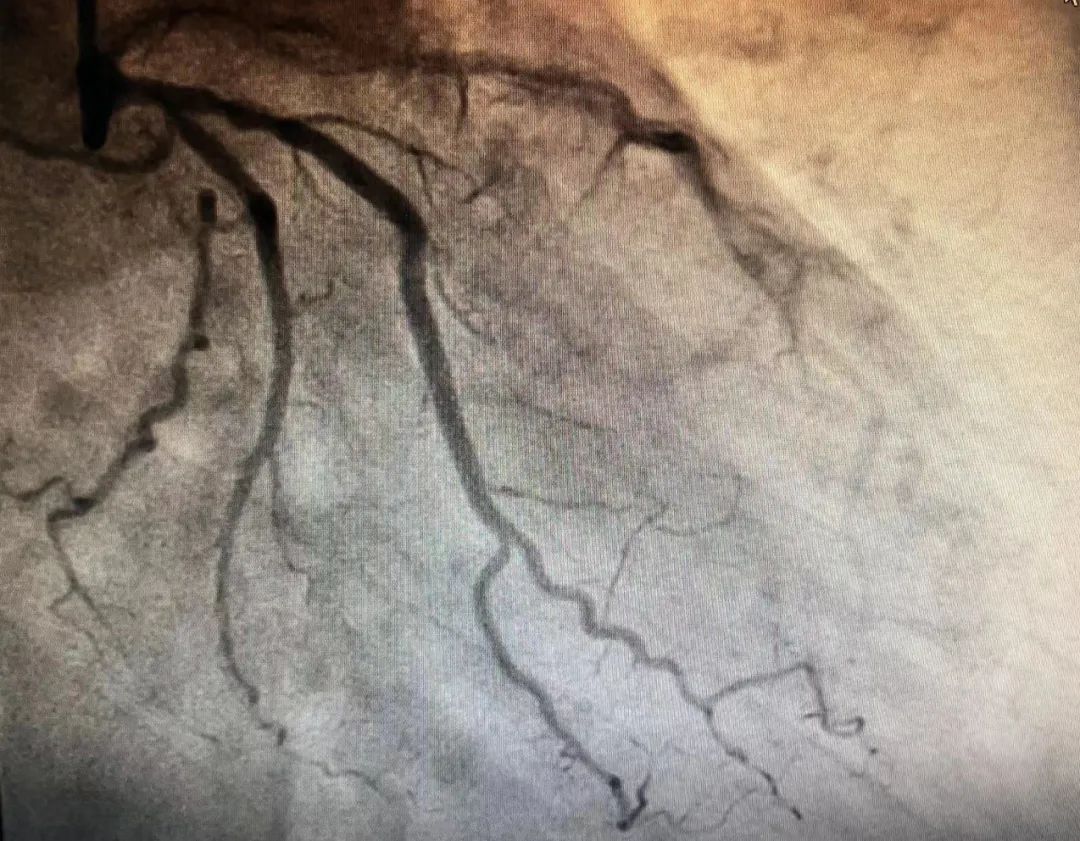

▲患者术后片子

在与患者家属沟通后,心血管内科团队为患者制定了个体化治疗方案,经过缜密的术前准备,于9月20日为患者实施手术。术中,副主任赵智敏通过导管将BioFreedom无聚合物药物涂层支架植入血管内病变部位,充分释放活性药物至血管壁内,持续扩张数分钟后,成功疏通了患者已经闭塞的血管,血流恢复正常,邹阿姨胸痛、胸闷症状明显消失,术后安返病房,家属对治疗效果十分满意!9月22日,邹阿姨胸痛症状基本消失,在家人的陪伴下办理了出院手续。